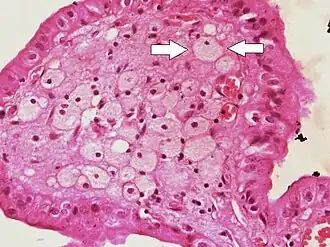

![]() Foam cells (one indicated by arrows) visible in the finger-like projections into the gallbladder lumen in a case of cholesterolosis | |

Foam cells, also called lipid-laden macrophages, are a type of cell that contain cholesterol. These can form a plaque that can lead to atherosclerosis and trigger myocardial infarction and stroke.[1][2][3]

Foam cells are fat-laden cells with a M2 macrophage-like phenotype. They contain low density lipoproteins (LDL) and can be rapidly detected by examining a fatty plaque under a microscope after it is removed from the body.[4] They are named because the lipoproteins give the cell a foamy appearance.[5]